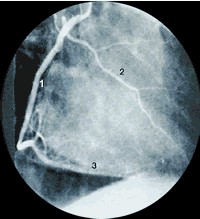

左侧位:左冠状动脉

左侧位可见到完整的前降支和间隔穿孔,它们和对角支不重叠。 1、第一边缘支 2、回旋支 3、对角支 4、前降支 5、间隔支 肋骨从一侧到另一侧,左侧稍低。 |